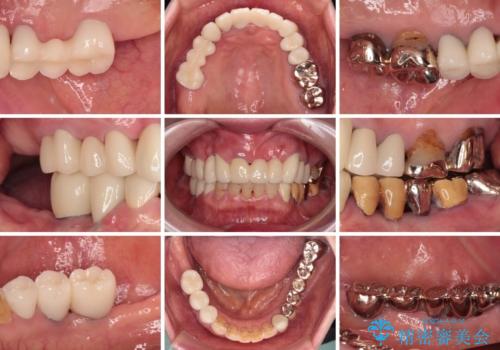

- 抜歯の必要な前歯や、以前治療した前歯のクラウンの外観を気にして来院された患者様です。

上顎犬歯や下顎大臼歯は、必要なところはインプラントを埋入することとしました。

クラウンが不適合であったり、根管治療の必要なほどの痛みのある歯であったり、見た目の気になる前歯などをオールセラミッククラウンに補綴治療を行うこととしました。